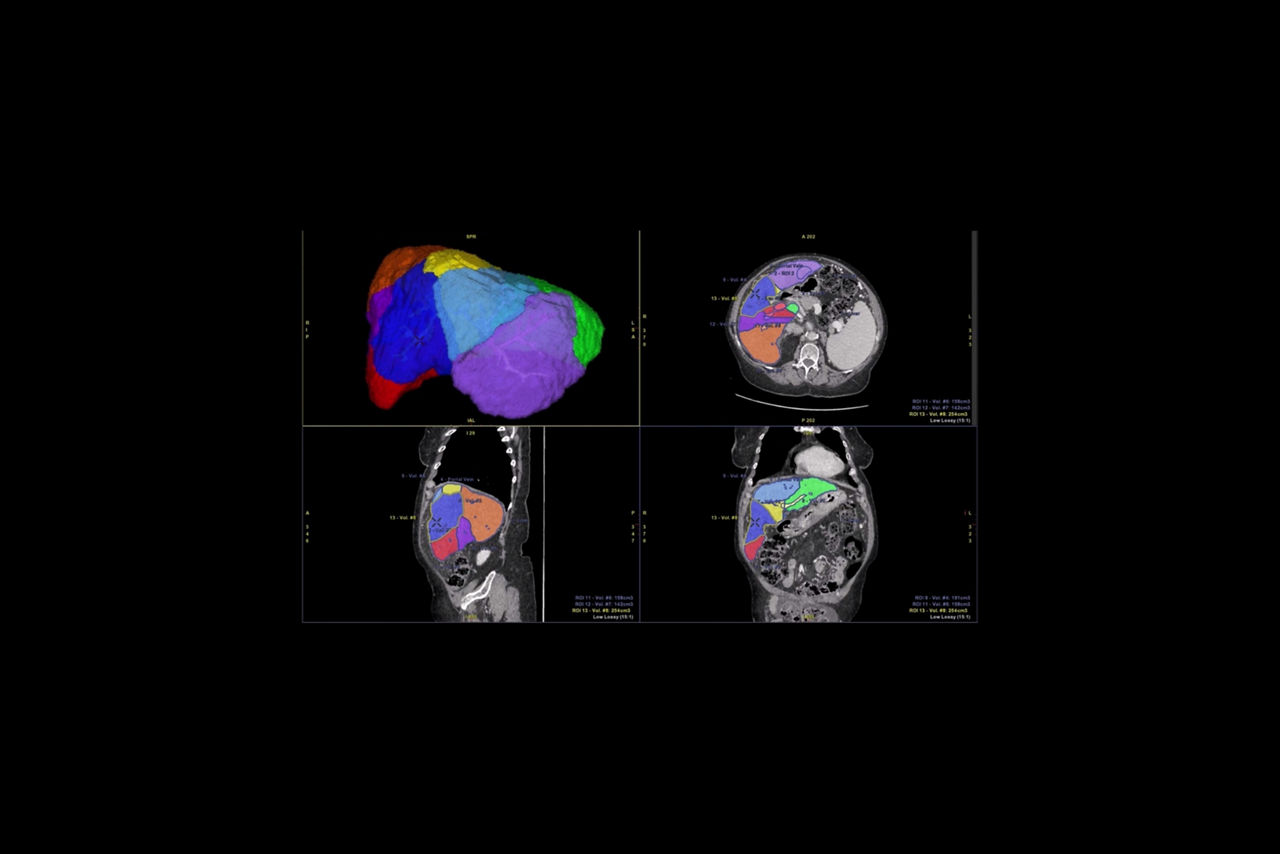

Automatic CT Liver segmentation based on deep learning.

Deep learning algorithm for automatic liver segmentation at different phases and hepatic artery segmentation

>95% overall success rate for automatic liver segmentation on the testing set

Guided workflow for assessing the complete liver anatomy to assist in surgical planning and lesion evaluation